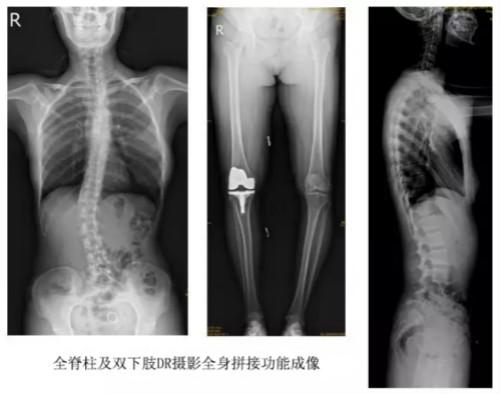

临床在诊治脊柱及下肢畸形时,往往采取矫正手术治疗。这就需要在对其进行手术前后,拍摄全脊柱或全下肢的X光片作为诊治依据,以便分析病情、制定手术方案和评估术后疗效。目前大部分医院使用的DR摄片机,因拍摄幅面受限,最大规格43cm,但成人的全脊柱长度一般约60cm,而全下肢更长,不能一次性拍摄出完整的全脊柱或全下肢的X光影像。以全脊柱摄片为例,各拍摄一张传统的颈椎、胸椎、腰椎的X片虽然就能观察到每个部位局部的侧弯情况,但不能观察到三者之间的连续性。因此传统X光片在这类疾病诊断上存在着一定的缺陷,无法更精准有效地进行临床诊断和治疗。

技术日新月异,随着DR全身拼接功能的可实现,有效解决了全脊柱及全下肢的完整成像。

以某院所摄X光片为例,对比传统摄片与全身拼接功能的区别:

传统X光片只能观察每个部位的局部情况,无法在统一体上进行连续、全面的观察,全脊柱及下肢全长片则能直观的看到整体形变。通过DR全身拼接功能实现的完整成像,为诊治脊柱及下肢畸形提供了完美的临床影像依据,对临床诊断、术前手术方案的制定和术后疗效的评估等临床应用具有十分重要的意义,有效满足了此类疾病临床诊断和治疗的要求。

通过以上对比,可以发现,在缺少DR全身拼接功能的条件下,传统X光摄片无法有效解决骨科常见疾病如脊柱侧弯及下肢畸形的临床诊断。在国家大力推进健康中国、人民不断增长的医疗需求的大背景下,医疗缺陷将不断被合理技术替代,因此从对立面评测,如今,没有全身拼接功能的DR就不是合格的DR。